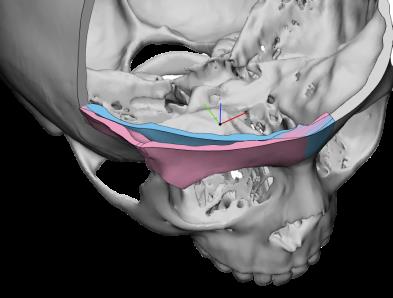

Correzione malformazioni cranio-facciali in età evolutiva ed adulta

Le alterazioni dello sviluppo dello scheletro facciale e delle ossa mascellari , di origina familiare o congenita , si caratterizzano anche con gravi modificazioni dell'occlusione con conseguenti problematiche funzionali ed estetiche. A questo proposito è molto importante intercettare la patologia di accrescimento osseo nell'età prepuberale ed eventualmente eseguire una terapia ortodontica dapprima intercettiva (per provare a risolvere le alterazioni dello sviluppo scheletro facciale) e successivamente di preparazione per l'eventuale intervento chirurgico ortognatico che si prefigge il compito di riposizionare il mascellare superiore e/o la mandibola nel rapporto spaziale anatomicamente corretto, con conseguente riallineamento masticatorio , funzionale ed estetico.